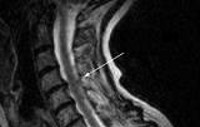

Из инструментальных методов применяются: рентгенография позвоночника для оценки состояния позвонков и межпозвоночных дисков, электромиография (исследование с магнитной стимуляцией, ЭМГ), с помощью которой оценивается прохождение электрического возбуждения по спинному мозгу; люмбальная пункция для исследования спинномозговой жидкости; МРТ позвоночника для визуализации спинного мозга; КТ позвоночника для визуализации костей позвоночника; КТ-ангиография для изучения кровеносных сосудов спинного мозга (выполняется с введением контраста).

Как только причину инфекционной миелопатии удается устранить, можно судить о том, каких результатов от лечения ждать. Важно определить, насколько болезнь повредила ткани спинного мозга, сохранилось или погибло его вещество. Это помогут сделать МРТ и электронейрография. Полное излечение возможно, если не было повреждения спинного мозга. Если заболевание продолжает развиваться, очаг инфекции не устранен, возможна полная потеря трудоспособности.